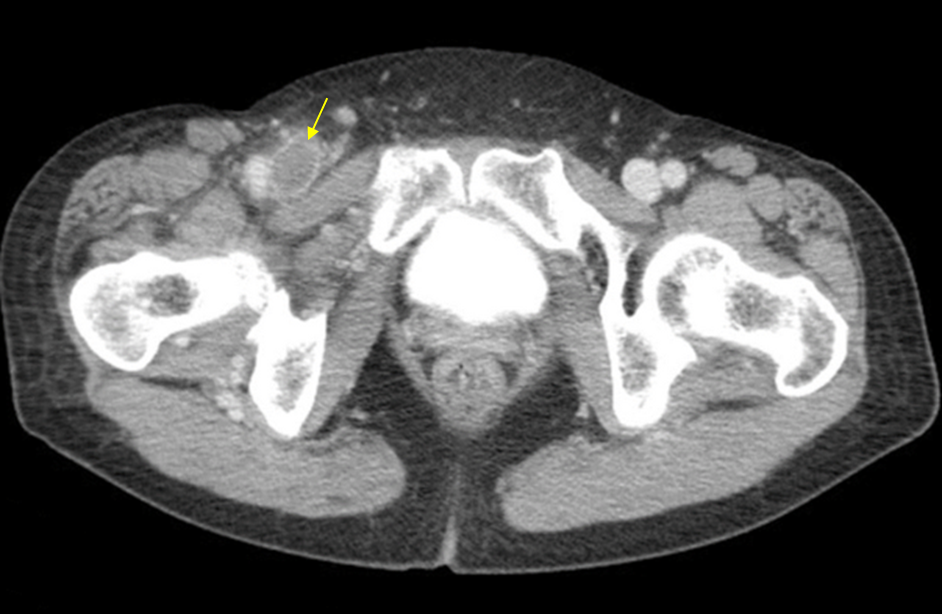

69세 여자가 5일 전부터 오른쪽 다리가 부어서 병원에 왔다. 혈압 130/90 mmHg, 맥박 64회/분, 호흡 14회/분, 체온 36.5℃이다. 다리 사진이다. 오른쪽 다리는 따뜻하고 오목부종이 있고 경미한 압통이 있다. 다리 컴퓨터단층촬영 사진이다. 진단은?

Img | 하지 CT: Rt. common iliac v. thrombotic occlusion |

하지부종, 압통, 따뜻한 피부 등 임상양상과 CT 소견으로 보아 DVT로 진단할 수 있다.

• 하지 CT에서도 Rt. common iliac v.에 thrombotic occlusion이 관찰되므로 DVT로 진단할 수 있다.